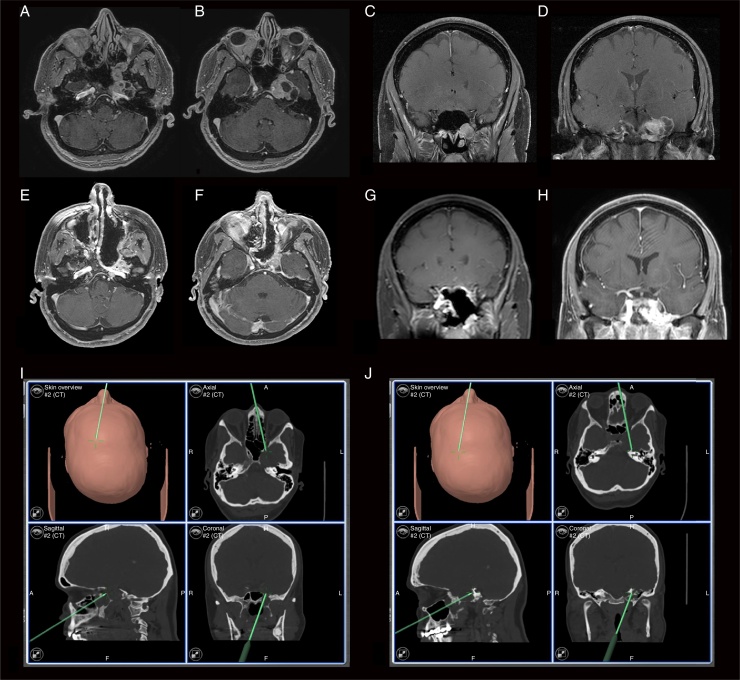

A previously healthy 60-year-old female patient came to our service complaining of reduced sensitivity in the left facial region for two months. On examination, the patient had hypoesthesia in the territory of the maxillary (V2) and mandibular (V3) branches of the trigeminal nerve. She had no other complaints or alterations at the physical examination. The radiological investigation carried out with cranial computed tomography and MRI showed a left-sided ventral and paramedian solid-cystic mass lesion in the skull base that exhibited heterogeneous contrast enhancement. There was intra and extracranial extension through the Vidian nerve canal, which was enlarged (Fig. 1).

Figure 1.

(A and B) Preoperative axial T1 MRI images with gadolinium; (C and D), preoperative coronal T1 MRI images with gadolinium; (E and F), postoperative axial T1 MRI images with gadolinium; (G and H), postoperative coronal T1 MRI images with gadolinium; (I), intraoperative neuronavigation image, showing the extension of the Vidian nerve canal (coronal); (J), intraoperative neuronavigation image showing posterior extent after lesion resection.